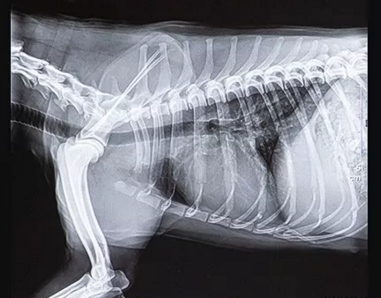

宠物dr拍摄效果图